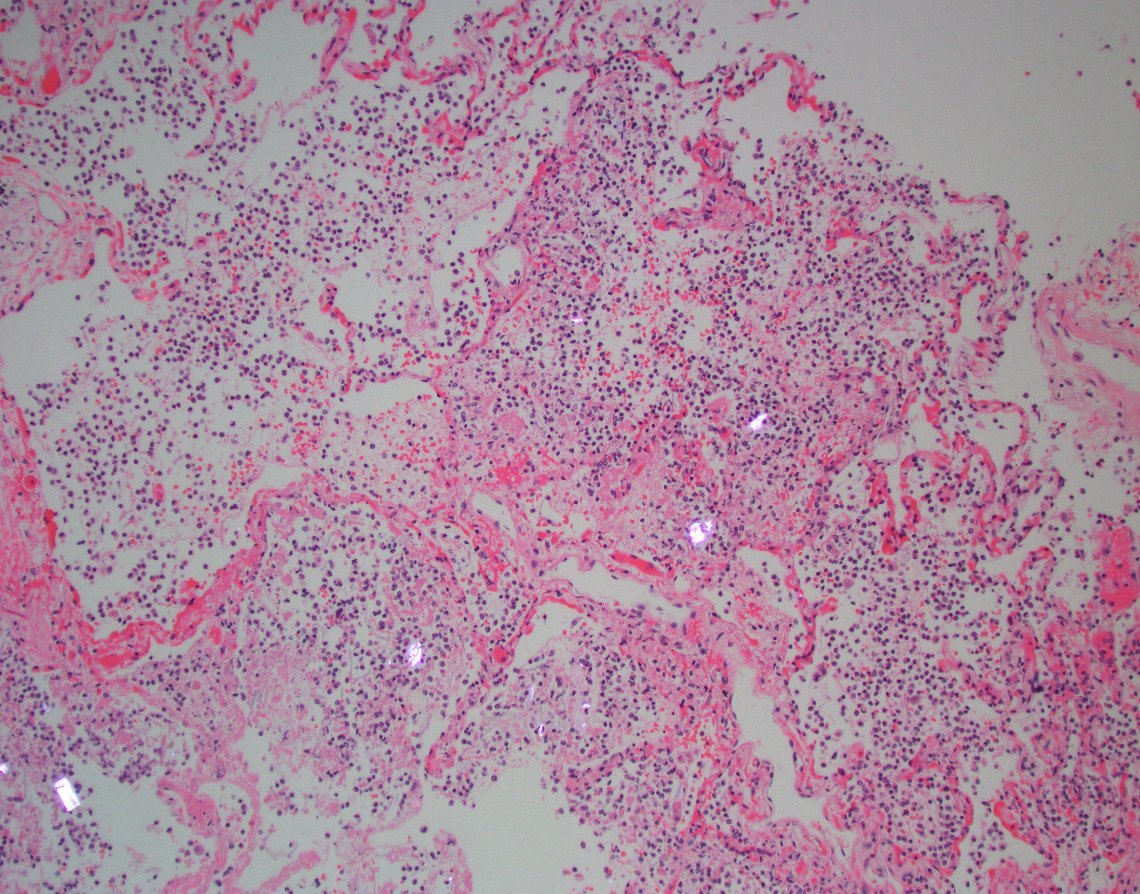

Surprising finding at autopsy (not an uncommon occurrence). Cardiac amyloidosis. Immediate cause of death in this case was aspiration pneumonia. Two reasons why it's good to have a polarizer handy when reviewing autospy slides. #cardiacpath